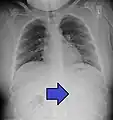

Airways

It is possible for a foreign body to enter the airways and cause choking.[5] A choking case can require the fast usage of basic anti-choking techniques to clear the airway.

In one study, peanuts were the most common obstruction.[6] In addition to peanuts, hot dogs, grapes, and latex balloons are also serious choking hazards in children that can result in death. A latex balloon will conform to the shape of the trachea, blocking the airway and making it difficult to expel with basic anti-choking techniques.[7]